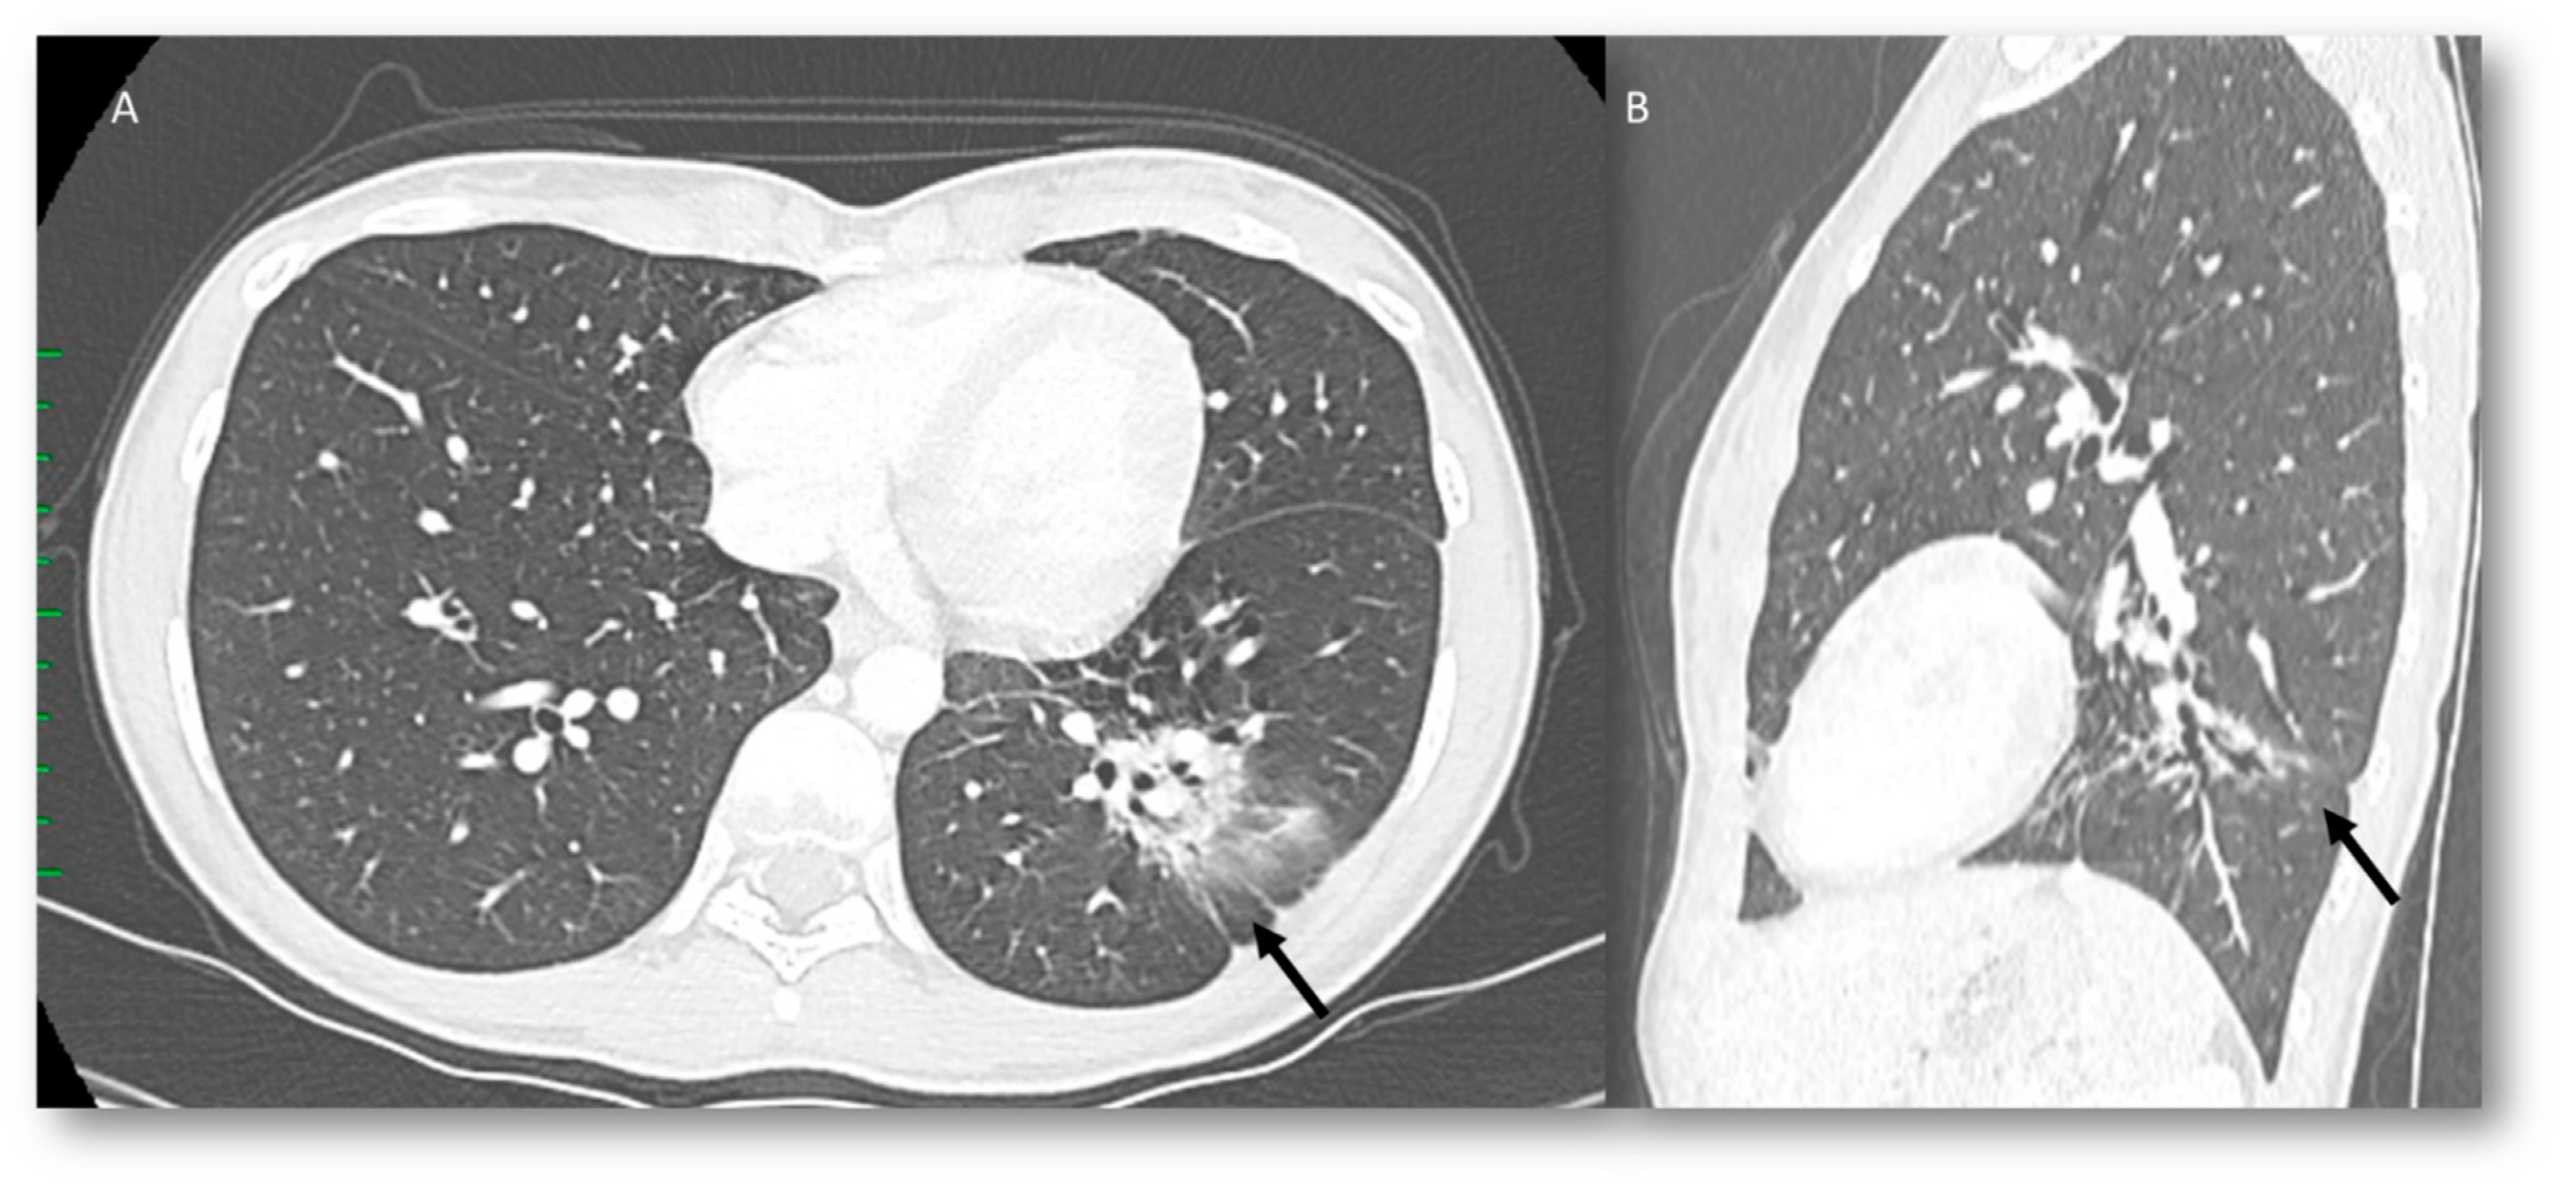

Radiation Recall Pneumonia

| RRP | Target area | Ground-glass opacities and consolidative opacities. | Unknown (A non-immune fixed drug reaction-like condition, dysregulated release of reactive oxygen species, abnormalities of tissue vasculature and impaired DNA repair). |